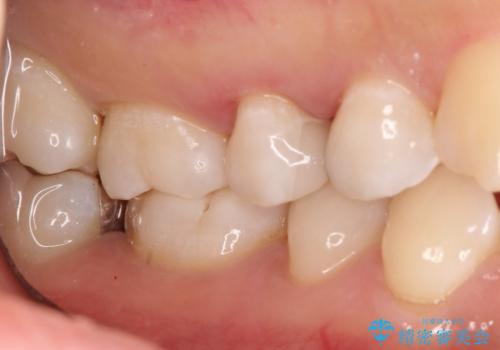

【セラミックインレー】むし歯の治療

- 定期検診にてむし歯を認めたため、セラミックインレーにて修復を行いました。

e-max プレスインレーにて修復治療を行っているため適合性及び審美性の高い治療を行うことができます